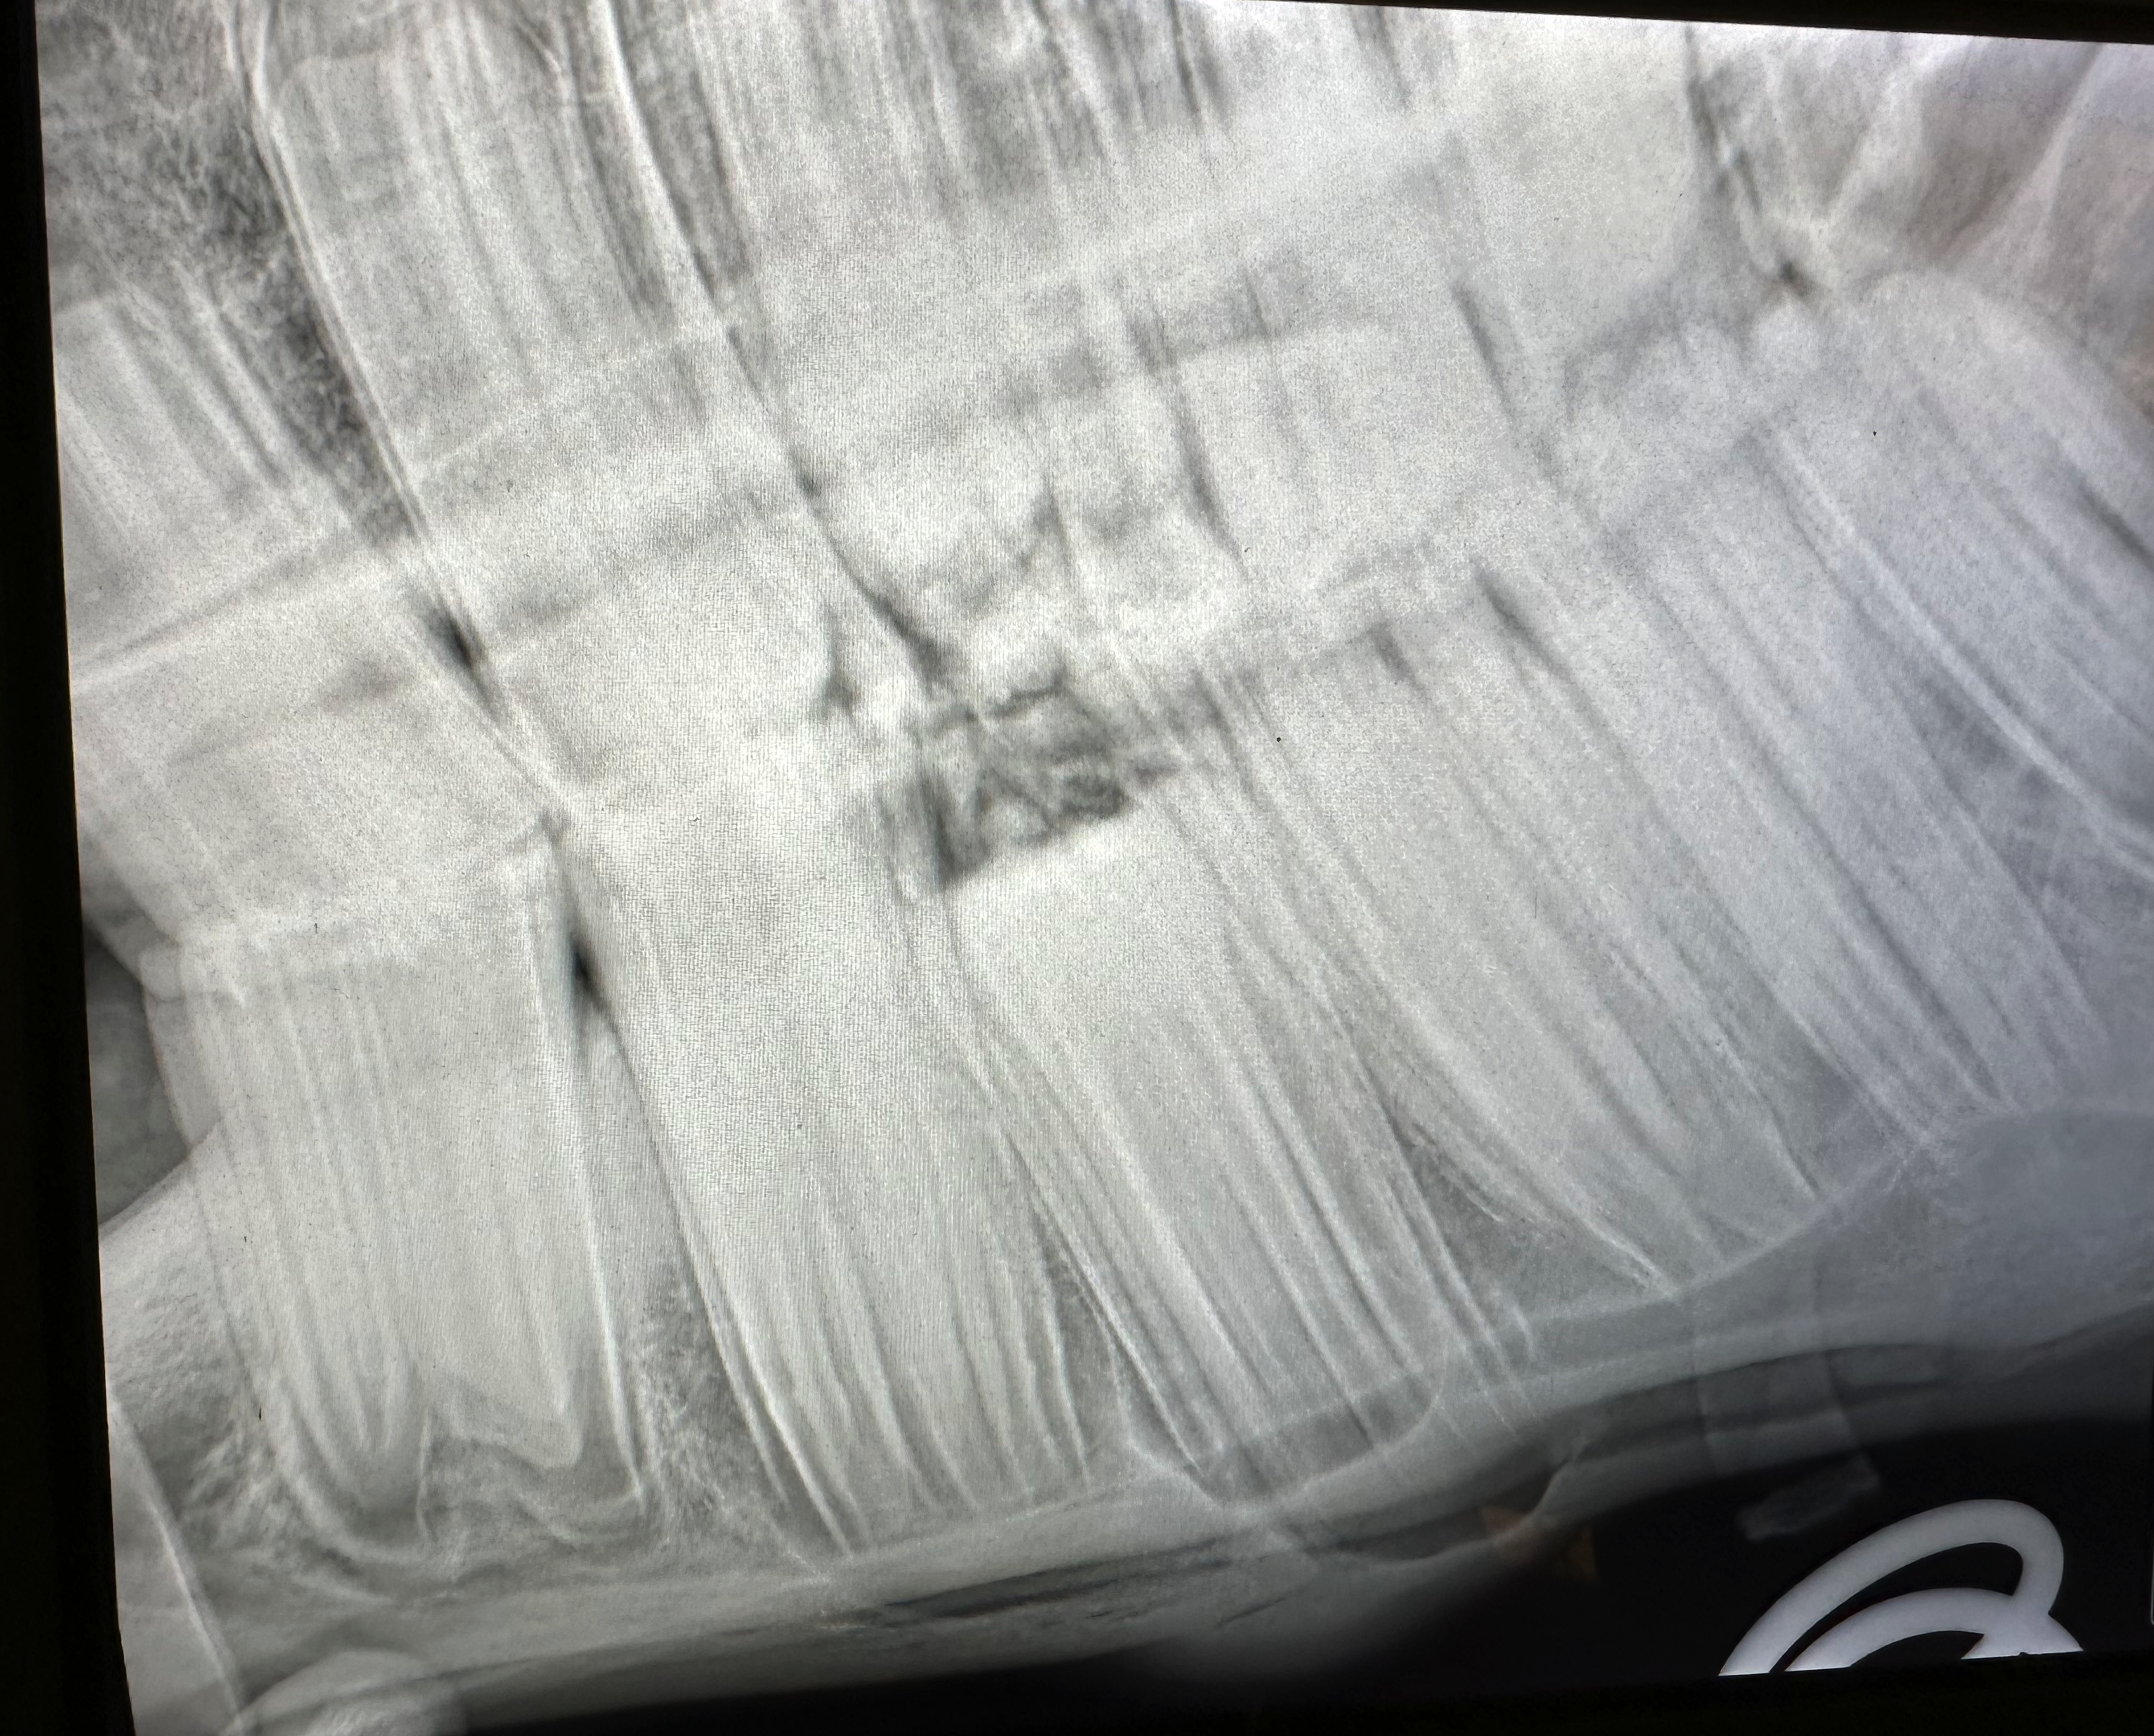

Jaarlijkse gebitscontrole is noodzakelijk voor de gezondheid en prestaties van uw paard.